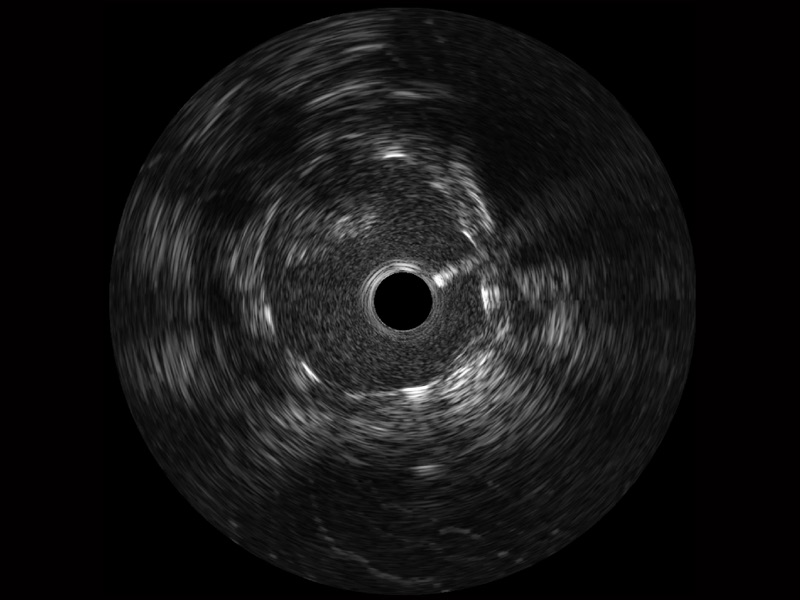

db真人体育官网宽频IVUS图像

对比传统IVUS导管成像,db真人体育官网宽频IVUS图像的近场支架梁显影更细腻,远场中膜外血管仍清晰可辨,兼顾远中近,兼顾分辨力与穿透深度